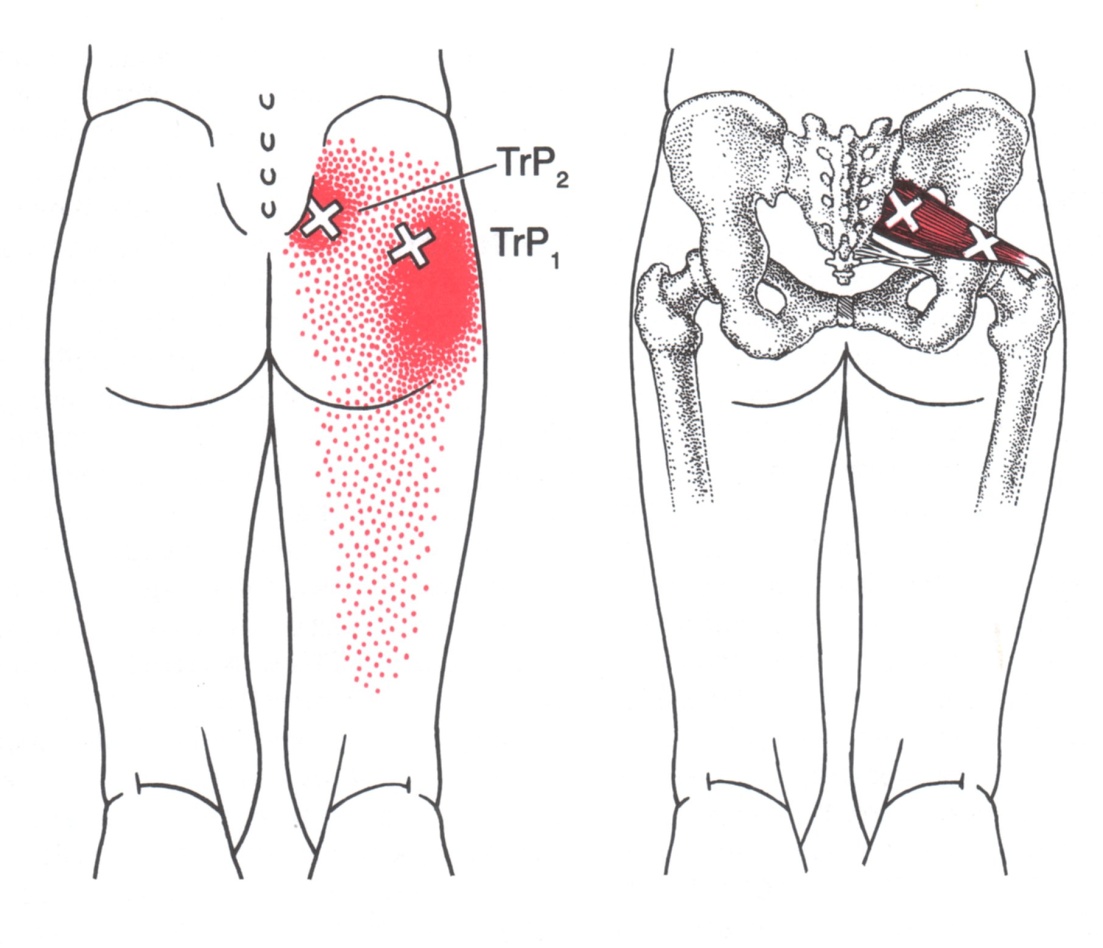

Ant.

Post. 소둔근의 Anterior part에 있는 TrPs에서의 방사통은 둔부 하외측 위와, 밑으로 대퇴의 측면, 무릎, 장딴지 및 발목으로 방사됩니다. Posterior fibers에 있는 trPs는 유사하지만 둔부의 하내측과 대퇴와 장딴지의 뒷 부분등 보다 후방으로 통증을 방사하는 경향을 갖습니다.

통증은 매우 고통스럽고 지속적인 양상으로 나타나며, TrPs의 위치가 깊이 위치하고 있고 원인 근육에서 매우 멀리 떨어진 곳에 통증이 나타나 TrPs를 찾기 어려운 경우가 많습니다.

앉아있을 때 보다 서있을 때 통증이 심화되는 경우가 많습니다.